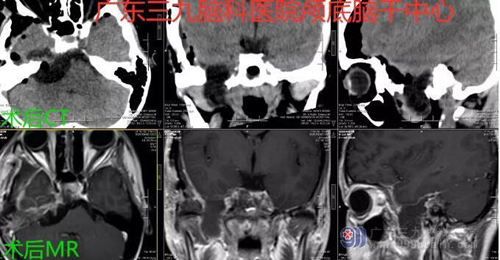

图1:术前CTA示右侧中后颅窝示囊性为主占位病变,向下累及右侧颞下窝,病变周围示细小血管影。双侧大脑前、中、后动脉主干显影良好,未见闭塞或畸形血管影。双侧颈内动脉、双侧椎动脉及基底动脉形态及密度未见异常。骨窗示右侧颞部骨质毛糙,右侧乳突密度增高。

2:术前MR示右侧中后颅窝示囊性为主占位病变,呈长、稍长T1长、稍长T2异常信号,FLAIR序列呈低信号及高信号,增强后囊壁异常强化,邻近右侧颞底硬脑膜增厚强化,向下累及右侧颞下窝,最大轴位层面范围52.4mm×38.8mm。邻近脑干及右侧桥臂受压移位。斜坡骨质T1WI高信号消失,与病灶邻近右侧颞骨示短T2低信号影,增强后呈轻度强化,鼻咽部粘膜增厚。

图3:术后CT及MR示右侧中后颅窝病变切除术后改变。